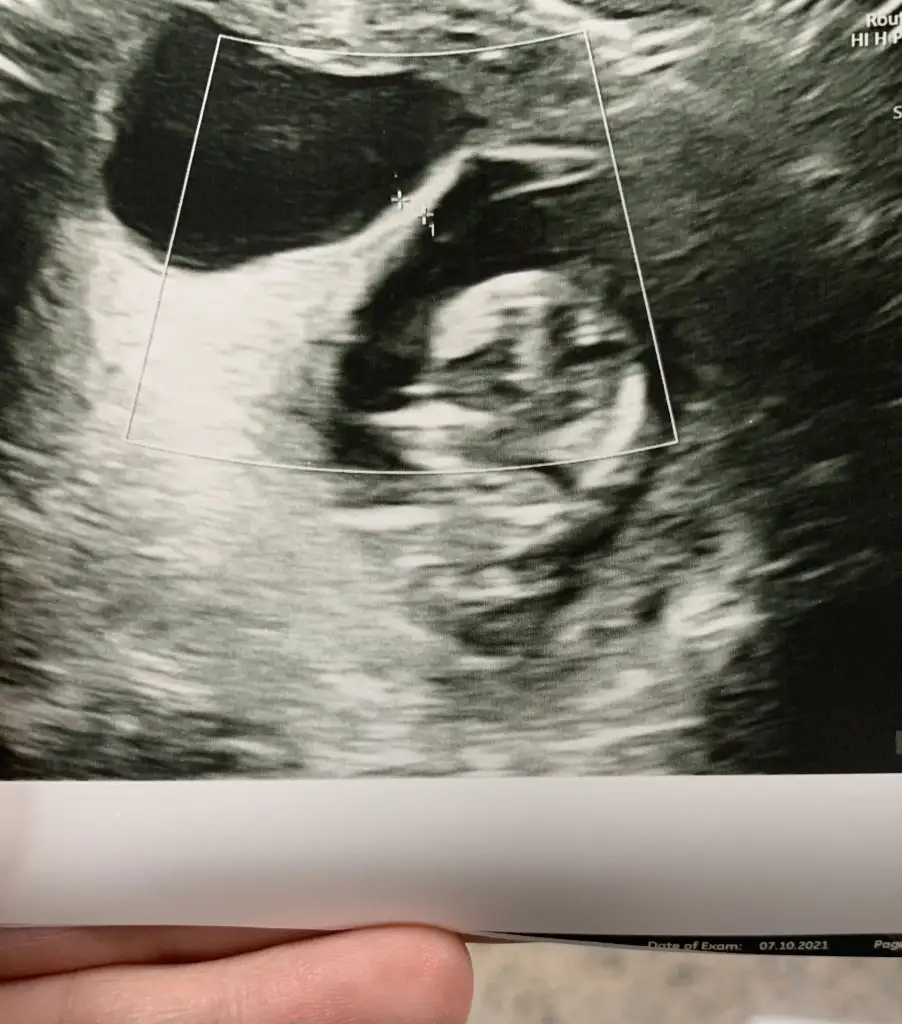

Ultrasonu da koydum. Baya rahmim ikiye bölünmüş gibi